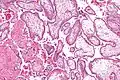

- Micrografía que muestra vellosidades coriónicas. Ampliación muy alta. Tinción H&E.